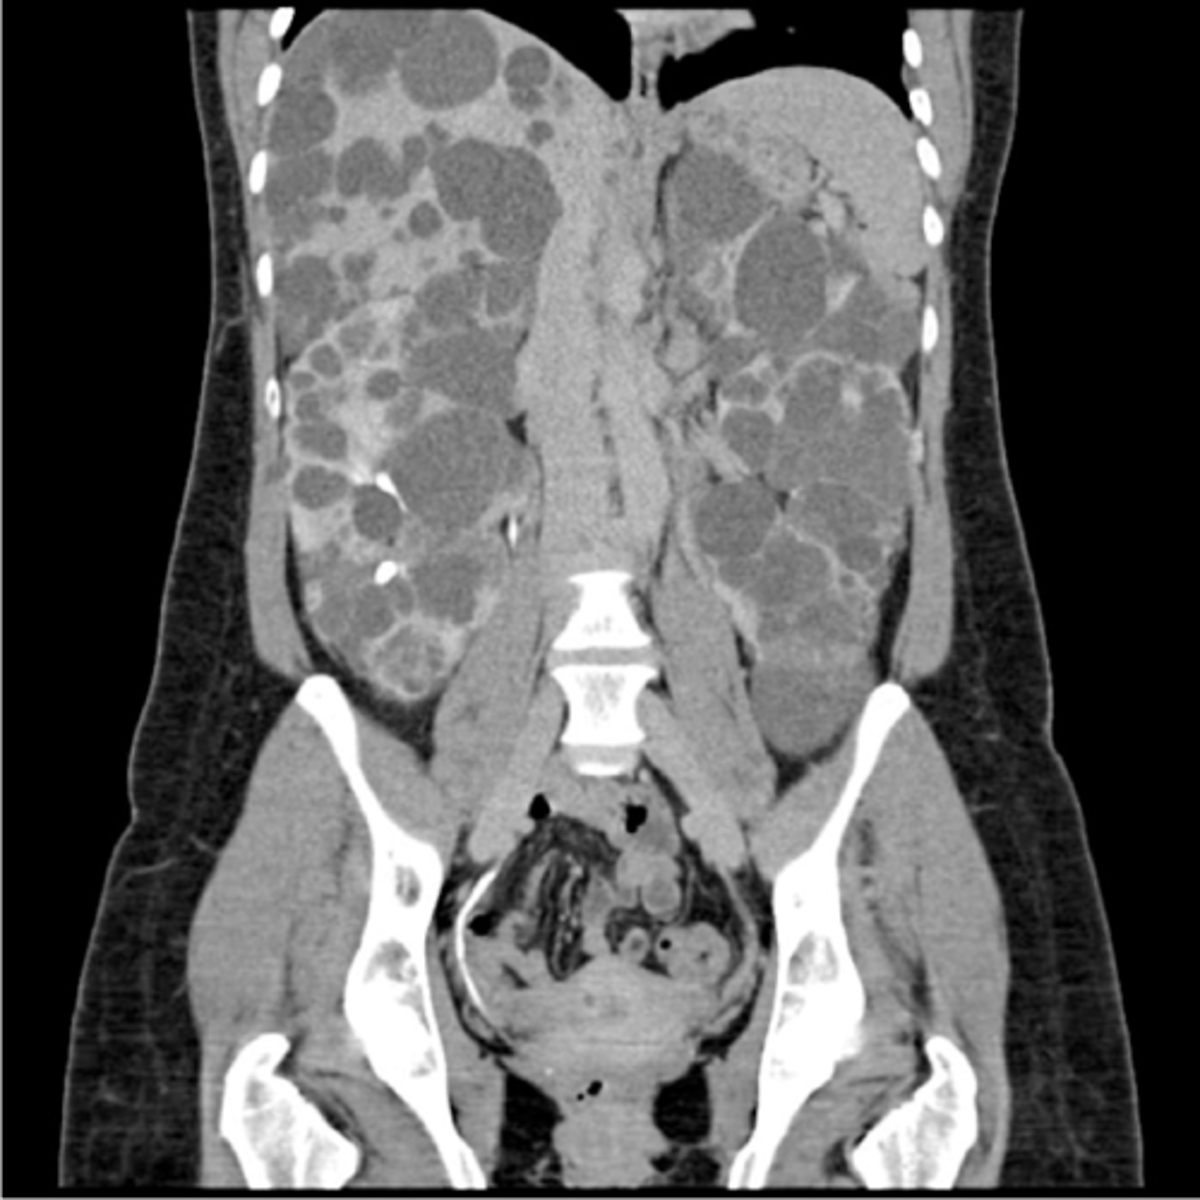

AD polycystic kidney disease

What disorder:

-85% of families have abnormality on chromosome 16 (PKD1 locus)

-remaining pts have abnormalities on chromosome 4 (PKD2 locus) --> less severe and often seen in late presenting

-Dx = imaging + Hx

-numerous cysts in cortex and medulla causing BL enlarged kidneys ultimately destroy kidney parenchyma

-Presentation = combo of flank pain, hematuria, HTN, urinary infection, calculi, progressive renal failure

autosomal dominant polycystic kidney disease

Clinical Course:

-renal function starts to decline usually by 30 y/o (GFR decreases 4-6 mL/min/year)

-gradual progression to ESRD

-pain from cysts and enlarged kidneys is common manifestation

-RFs for progression to ESRD = genotype PKD1, HTN, early onset protienuria and hematuria, M gender, increasing kidney size and rate of growth, LV mass index, proteinuria alone, FMHx progression to ESRD

-cause of death = cardiac (36%), infection (24%), neurologic (12% -- either ruptured intracranial (berry) aneurysm or hypertensive intracerebral hemorrhage)

ID